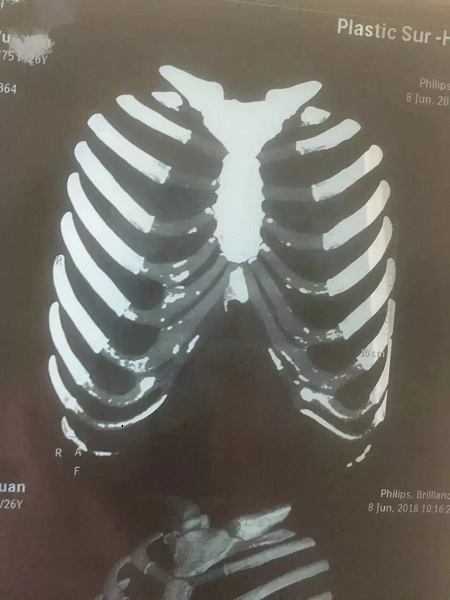

▼鈣化肋軟骨和未鈣化肋軟骨的影像區(qū)別

如上圖所示,鈣化了的肋軟骨和硬骨一樣,都是呈同樣密度的白色顯示,而正常的肋軟骨密度顯示是透明狀。

▼輕微鈣化的肋軟骨